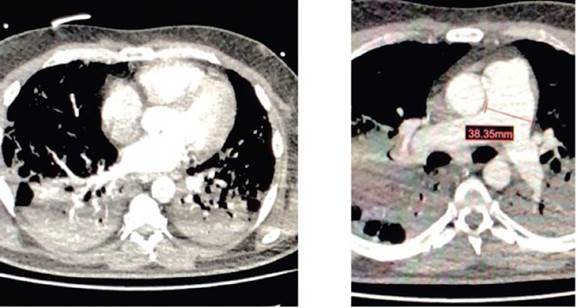

Ante la sospecha de tromboembolismo pulmonar, se realizó una angiotomografía de las arterias pulmonares (Imagen 1). El diagnóstico fue defectos de llenado central de las arterias pulmonares principales; múltiples trombos en las arterias pulmonares lobares, así como signos radiológicos sugestivos de consecuencias hemodinámicas en las cámaras del corazón derecho.

Defectos de llenado central en ambas arterias pulmonares principales y presencia de trombos. Signos radiológicos sugestivos de consecuencias hemodinámicas en las cámaras del corazón derecho: calibre de la arteria pulmonar hasta de 38mm, rectificación del tabique interventricular. FUENTE: Autores.

IMAGEN 1 Angiotomografía: tromboembolismo pulmonar agudo.